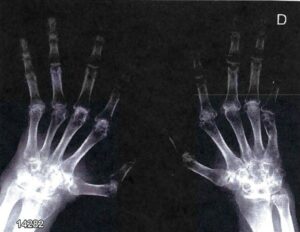

Tra le complicanze vi sono anche la febbre reumatica (coinvolgimento cuore, articolazioni, sistema nervoso, cute) e la glomerulonefrite post-streptococcica (patogenesi non legata alla presenza del batterio ma a fenomeni immunologici per la presenza della proteina M dello streptococco con epitopi molto simili a quelli della sinovia e delle valvole cardiache). Oggi queste due complicanze sono piuttosto rare per via dell’utilizzo di antibiotici che trattano l’infezione.